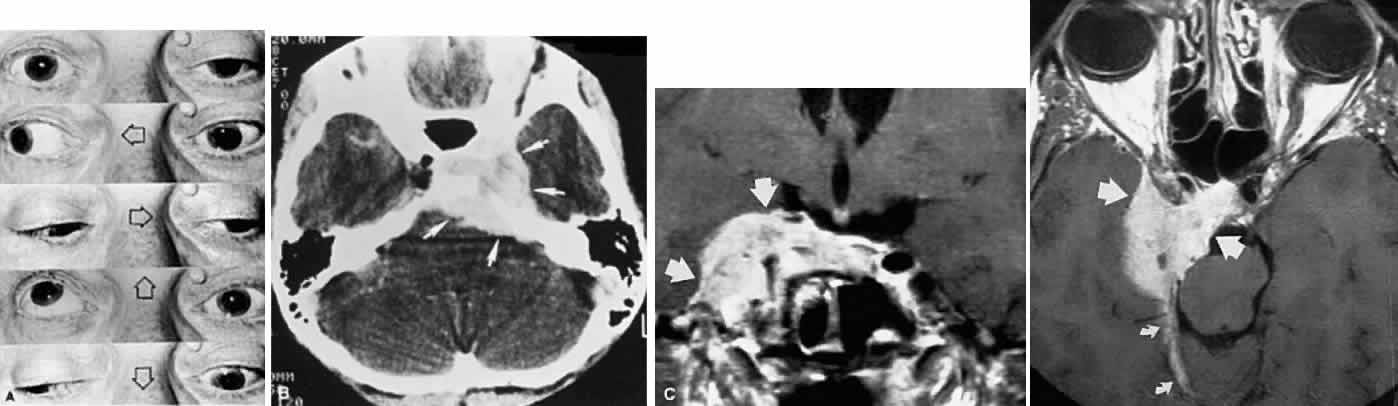

In the cavernous sinus, the abducens nerve may be involved in combination with the ophthalmic-trigeminal, third, or fourth nerves. Abducens monoparesis is frequent with cavernous sinus lesions, perhaps related to the nerve's location within the sinus, inferolateral to the carotid artery and unsupported by the dural wall of the sinus.19,20 Isolated abducens palsy occurs with carotid-cavernous fistulas (especially with spontaneous dural shunts21) and intracavernous aneurysms20 (Fig. 7), and is the earliest indication of contralateral spread of cavernous sinus thrombosis. Sixth nerve palsy accompanied only by ipsilateral Horner's syndrome also points to the cavernous sinus, since the ocular sympathetics from the carotid plexus may be simultaneously involved.22

FASCICULAR LESIONS Deficits of the oculomotor fasciculus are usually identified by the accompanying brain stem signs. Oculomotor palsy with contralateral hemiplegia (Weber syndrome) indicates involvement of the corticospinal tracts. Contralateral ataxia and intention tremor (Benedikt syndrome) indicates involvement of the red nucleus (see Fig. 2). Nothnagel syndrome is an eponym given when signs of both Weber and Benedikt syndromes are present. Midbrain vascular accidents account for most fascicular defects. Ksiazek84 shed some light on the fascicular arrangement of the oculomotor nerve based on two patients with partial oculomotor paresis, each with pupillary mydriasis, significant inferior rectus paresis, and medial rectus paresis. Neuroimaging revealed a lesion in the fascicular portion of the nerve, thus indicating the proximity of these fibers in the fasciculus. Monocular elevator paresis (superior rectus and inferior oblique) in mass compression of the oculomotor fasciculus has also been reported.85 In this regard, Castro and associates86 proposed the mediolateral somatotopy of the oculomotor fascicular fibers within the mesencephalon with the inferior oblique and superior rectus muscles being most lateral, and the pupilloconstrictor fibers and inferior rectus being most medial. The levator palpebrae fascicles are in an intermediate location between the superior rectus and medial rectus fascicles. INTERPEDUNCULAR LESIONS Basal lesions, including the rare rostral basilar artery aneurysm, may encroach on the oculomotor nerves as they exit in the interpeduncular space. Such slow-growing aneurysms, either saccular or fusiform, may present as partial oculomotor palsies with or without involvement of pyramidal tracts, and without subarachnoid hemorrhage.87 Aneurysms of the posterior communicating artery, on the other hand, are probably the most common lesions causing acute spontaneous oculomotor palsies (Fig. 12). According to Hyland and Barnett,88 the oculomotor palsy that occurs with posterior communicating aneurysm is not necessarily due to mass effect per se, but rather is attributed to hemorrhage that suddenly enlarges the aneurysmal sac to which the oculomotor nerve is adherent, or to hemorrhage into the substance of the nerve itself. Most patients present, therefore, with an intensely painful, complete unilateral oculomotor palsy in association with other signs and symptoms of subarachnoid hemorrhage. Few patients with symptomatic posterior communicating aneurysms are found in office waiting rooms: they are usually obtunded or comatose in emergency rooms. Involvement of pupillary fibers is such a consistent finding in third nerve palsies due to bleeding aneurysms that most clinicians concur in this useful dictum: a pupil-sparing, but otherwise complete, third nerve palsy is very unlikely to be due to posterior communicating aneurysms. Careful pupil evaluation may disclose subtle abnormalities in “apparent pupil-sparing,” especially in cases of aberrant regeneration or with chronic cavernous sinus lesions. Generally, in patients at least 50 years of age or older, an acute, isolated, painful oculomotor palsy that spares the pupil is caused by intraneural ischemia; nevertheless, these patients must be carefully observed for further evolution. In our opinion, an acute complete oculomotor palsy with moderate to major mydriasis, even when diabetes is present, is an indication for cerebral arteriography. It should be emphasized that magnetic resonance angiography may not detect aneurysms smaller than 3 to 4 mm.89 The clinical management of patients with relative pupil-sparing third nerve palsies remains in debate. Observation alone arguably is appropriate management of such patients; however, since practically every conceivable combination of partial ophthalmoplegia and pupillary abnormality has been reported in aneurysmal compression of the third nerve, it is better to err on the side of caution and perform angiography more frequently. It is incumbent upon the physician to evaluate carefully the proportion of ophthalmoplegia and ptosis in relation to the degree of pupillary abnormality when deciding appropriate workup of these patients. Again, the increasing sensitivity of magnetic resonance angiography has not yet entirely replaced formal angiography. Certainly, neurosurgical intervention requires conventional cerebral arteriography before surgical treatment. Capó and colleagues90 pointed out that the interval from onset to maximal ophthalmoplegia does not differentiate between microvascular (3.3 days) and aneurysm (3 days), but that failure to recover within 4 to 8 weeks requires further evaluation. Other partial oculomotor palsies occur regularly with cavernous sinus masses and parasellar syndromes (see below), accompanied by variable pupillary findings. Furthermore, both acute and chronic lesions may produce incomplete palsy of the superior division (supplying levator palpebrae and superior rectus muscles) or of the inferior division (medial and inferior recti, inferior oblique and pupillomotor fibers). If pain or first trigeminal division numbness are absent, and if the pupil is uninvolved, such fractional oculomotor pareses are regularly misinterpreted as myasthenia or local orbital inflammations. Guy et al91 described five patients with isolated ptosis and elevator paresis in abduction, consistent with selective “superior division” involvement. They also discussed five previously reported cases with the following respective diagnoses: (1) intracavernous aneurysm (usually with associated Horner's syndrome) and basilar artery aneurysm; (2) diabetic ophthalmoplegia; (3) meningitis; (4) dural lymphoma; and (5) postsurgical manipulation of parasellar structures. In essence, there was little anatomic correlation with the physical separation into superior and inferior oculomotor trunks that occurs in the cavernous sinus. Moreover, two patients sustained superior division palsies during surgical manipulation of the subarachnoidal portion of the oculomotor nerve trunk. A number of cases of inferior rectus paresis, isolated or in combination with ipsilateral or contralateral superior rectus paresis, have been construed as focal lesions involving the rostral portion of the oculomotor nuclear complex.80–82 Oculomotor palsy following head trauma is not rare, but probably occurs less frequently than traumatic fourth nerve palsies. As a rule, such closed-head injury causes loss of consciousness and is accompanied by skull fracture, but this is not invariable. Injury to the ocular motor nerves in road accidents was studied by Heinze,92 who dissected the cadavers of 21 fatal cases. He found that the relationship of frontal or temporal fractures to neural damage was unpredictable. In fact, intact nerves were encountered adjacent to gross fracture sites. The oculomotor nerve was damaged at three locations: (1) avulsion of the rootlets at their ventral exit from the brain stem; (2) contusion necrosis of the most proximal portion of the nerve trunk; and (3) intraneural and perineural hemorrhage of the nerve trunks at the level of the superior orbital fissure. Of great interest are Heinze's findings of focal hemorrhages in extraocular muscles, usually associated with fractured orbital bones. Eyster et al93 reported three patients with large basicranial tumors, who presented with oculomotor palsies precipitated by mild blows to the head that were insufficient to cause fracture or loss of consciousness. The oculomotor nerves were encased and stretched by tumor, which apparently rendered these tethered nerves vulnerable when innocent head blows abruptly shifted the brain. The authors pointed out that such atypical presentations of intracranial tumors may further mimic aneurysms, since subarachnoid hemorrhage does occasionally occur with tumors. Neetens94 reported an additional three cases of oculomotor nerve palsies after minor trauma in the presence of basal intracranial tumors; the trochlear nerve was involved in all three cases, and in two cases the oculomotor nerve was partially affected. Walter et al95 reported two instances of minor head trauma resulting in complete third nerve palsies attributed to occult posterior communicating artery aneurysms. We have seen a 45-year-old school teacher who experienced an immediate right abducens palsy when playfully slapped on the back of the head; within weeks, other cranial nerve palsies announced the presence of diffuse meningeal spread of carcinoma. In the United States, basilar meningitis is rare, but was formerly encountered with tuberculosis and syphilis. When the third nerve is involved in such cases, progressive defects are the rule and other cranial nerve palsies are commonly found. Oculomotor palsy may especially occur with meningitides in infants, including instances of viral and bacterial (e.g., Streptococcus pneumoniae, Haemophilus influenzae) infections.96 Oculomotor nerve compression by the proximal segment of the posterior cerebral artery, or by the uncus against the petroclinoid ligament, can be seen with increasing cerebral edema or with an ipsilateral expanding supratentorial mass, and it is often heralded by unilateral pupillary dilation (Hutchinson pupil). Progression rapidly leads to complete ocular motor nerve palsy. Keane97 reviewed the ocular motor signs of tentorial herniation, which include anisocoria and parasympathetic pupillary abnormalities, unilateral or bilateral ptosis, internuclear ophthalmoplegia, vertical gaze paresis, and partial third nerve palsies. CAVERNOUS SINUS LESIONS The oculomotor nerve may be involved by inflammatory disease, tumor, aneurysm, arteriovenous fistula, or thrombosis at the level of the cavernous sinus. The third nerve is usually involved in combination with the fourth, sixth, and ophthalmictrigeminal nerves, and accompanying sympathetic paresis may minimize pupillary dilation. The syndrome of the cavernous sinus, therefore, includes multiple ocular motor nerve palsies and pain or numbness in the first trigeminal division. In practice, lesions involving primarily the superior orbital fissure produce signs and symptoms that, with the possible exception of proptosis, cannot be distinguished from those of the anterior cavernous sinus. In particular, dural carotid cavernous fistulas that drain primarily into the inferior petrosal sinus may cause third nerve pareses without significant orbital congestion.98 Third nerve palsies due to lesions in the cavernous sinus tend to be partial in that all muscles innervated by the oculomotor branches need not be involved. This is especially true of pupillomotor fibers, such that the pupil may be normal or minimally involved. This “pupil- sparing” is offhandedly attributed to the superimposition of sympathetic paresis (Horner syndrome), but appropriate pharmacologic tests rarely substantiate this explanation (see below, Parasellar Syndrome). More likely, slowly expanding masses (e.g., infraclinoid aneurysm, meningioma) functionally spare the pupilloconstrictor fibers in the intracavernous portion of the oculomotor nerve. In addition, the levator, superior, inferior, and medial recti may be involved in unequal degrees, but progressive paresis evolves. (Once again, myasthenia must be suspected in any nonpainful, pupil-sparing, nonproptotic ophthalmoplegia, with or without ptosis.) Cavernous sinus lesions are further discussed below. Primary neurinoma of the oculomotor nerve is a relatively rare lesion that should be considered in children or young adults with insidious third nerve palsy. These may occur in the cavernous or interpeduncular portion of the nerve (Fig. 13).99,100